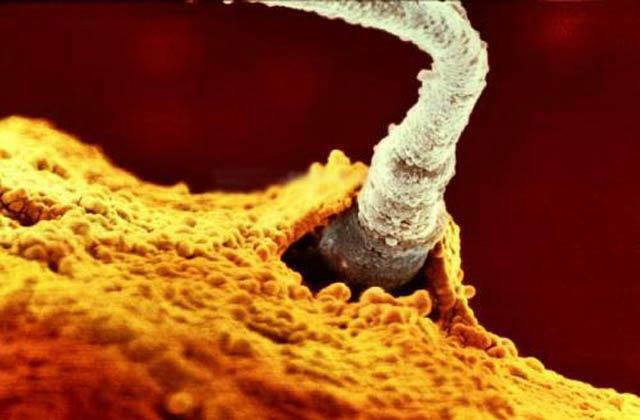

5.精子努力鑽入卵子當中, 終於順利打敗兩億個精子,成為最後的冠軍了!

6.獲勝的瞬間,恭喜恭喜真的恭喜~